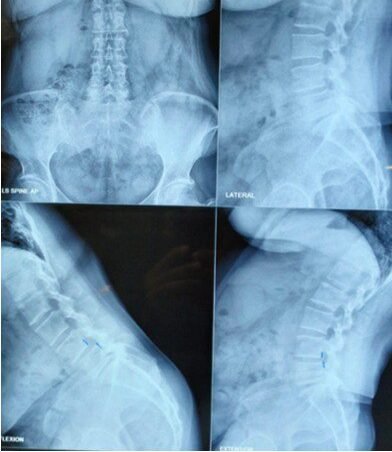

Diagnosis

- X-rays (standing lateral views) to assess slippage

- MRI to evaluate nerve compression and discs

- CT scan for bony defects (especially pars defects)

- Dynamic X-rays to assess instability